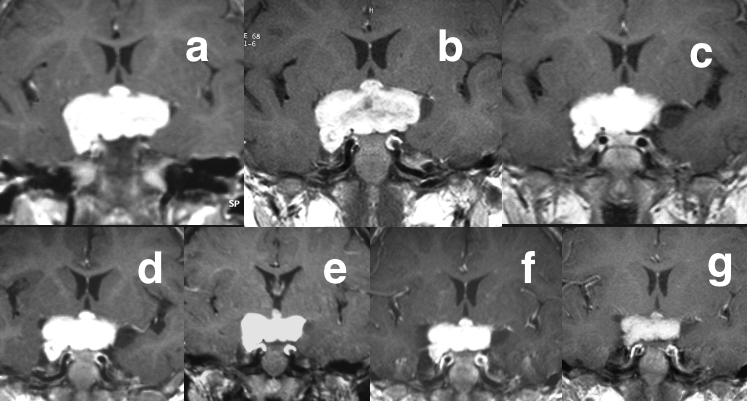

シスプラチン/ビンクリスチンを用いた化学療法の効果を示すMRI画像です。aは治療前,gは6コース終了時点(2歳)で,各々のMRIは各コース終了時点で撮影されています。このようにはっきりした腫瘍縮小効果は数カ月にわたる経過でゆっくりと観察されるので,1コースか2コースの化学療法であまり小さくならないからといって,化学療法が有効でないと即断してはいけません。この子は2001年水平性眼振で発症,1歳で発症して15年が経ちますが視力視野はほとんど正常で,腫瘍はほぼ消失,元気に暮らしています。